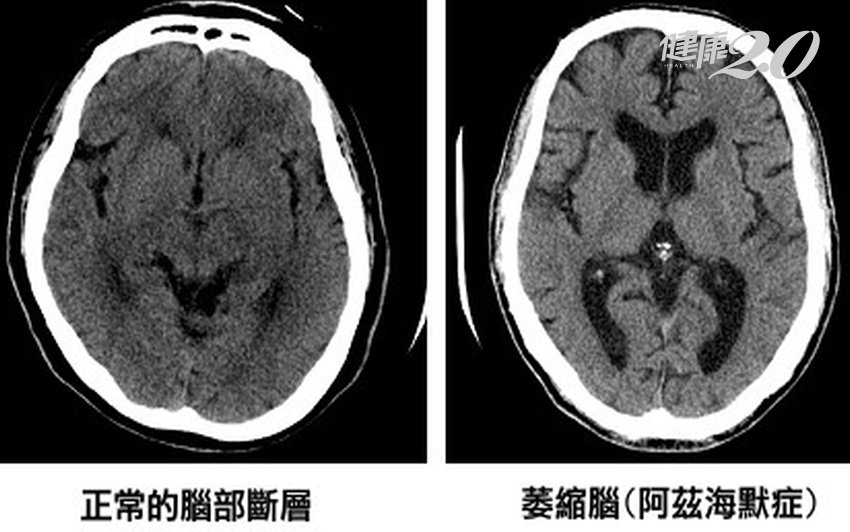

李建欣指出,失智症種類主要可分為:退化型(阿茲海默氏症屬於其中一種)、血管型、混和型與其他原因造成。其中以阿茲海默氏症最常見。

類澱粉蛋白斑塊為阿茲海默氏症中最主要病理特徵,患者大腦中會有此斑塊堆積。過往只能在患者過逝後進行解剖確認。

如今可透過類澱粉蛋白正子造影,藉由特殊顯影劑及正子造影「點亮」辨識大腦中的β-澱粉樣蛋白神經炎斑塊分布情形,在阿茲海默症初期時,輔助醫師確診或排除阿茲海默症,因此病患不再因病情發現太晚受苦,錯失預防病情惡化良機,造成無法挽回遺憾。